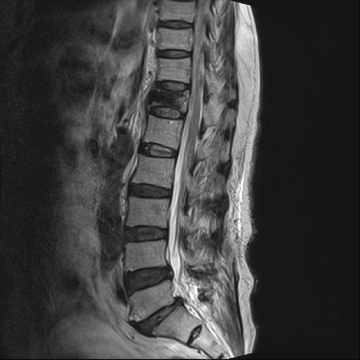

단, 골절이 심하여 척추뼈가 신경을 심하게 압박하는 경우나

척추뼈의 골절이 심한 파열 골절의 경우는 수술적 치료가 필요할 수 있습니다.

수술적 치료는 척추뼈가 움직이지 않고 신경을 자극하지 않도록 하는 고정술을 주로 시행합니다.

척추 고정술 치료 방법

2020.06.09

2020.08.11

ㆍ환자 동의를 받은 자료이며, 이미지 사진은 실물과 다를 수 있습니다.

ㆍ모든 자료는 새움병원 자료입니다.